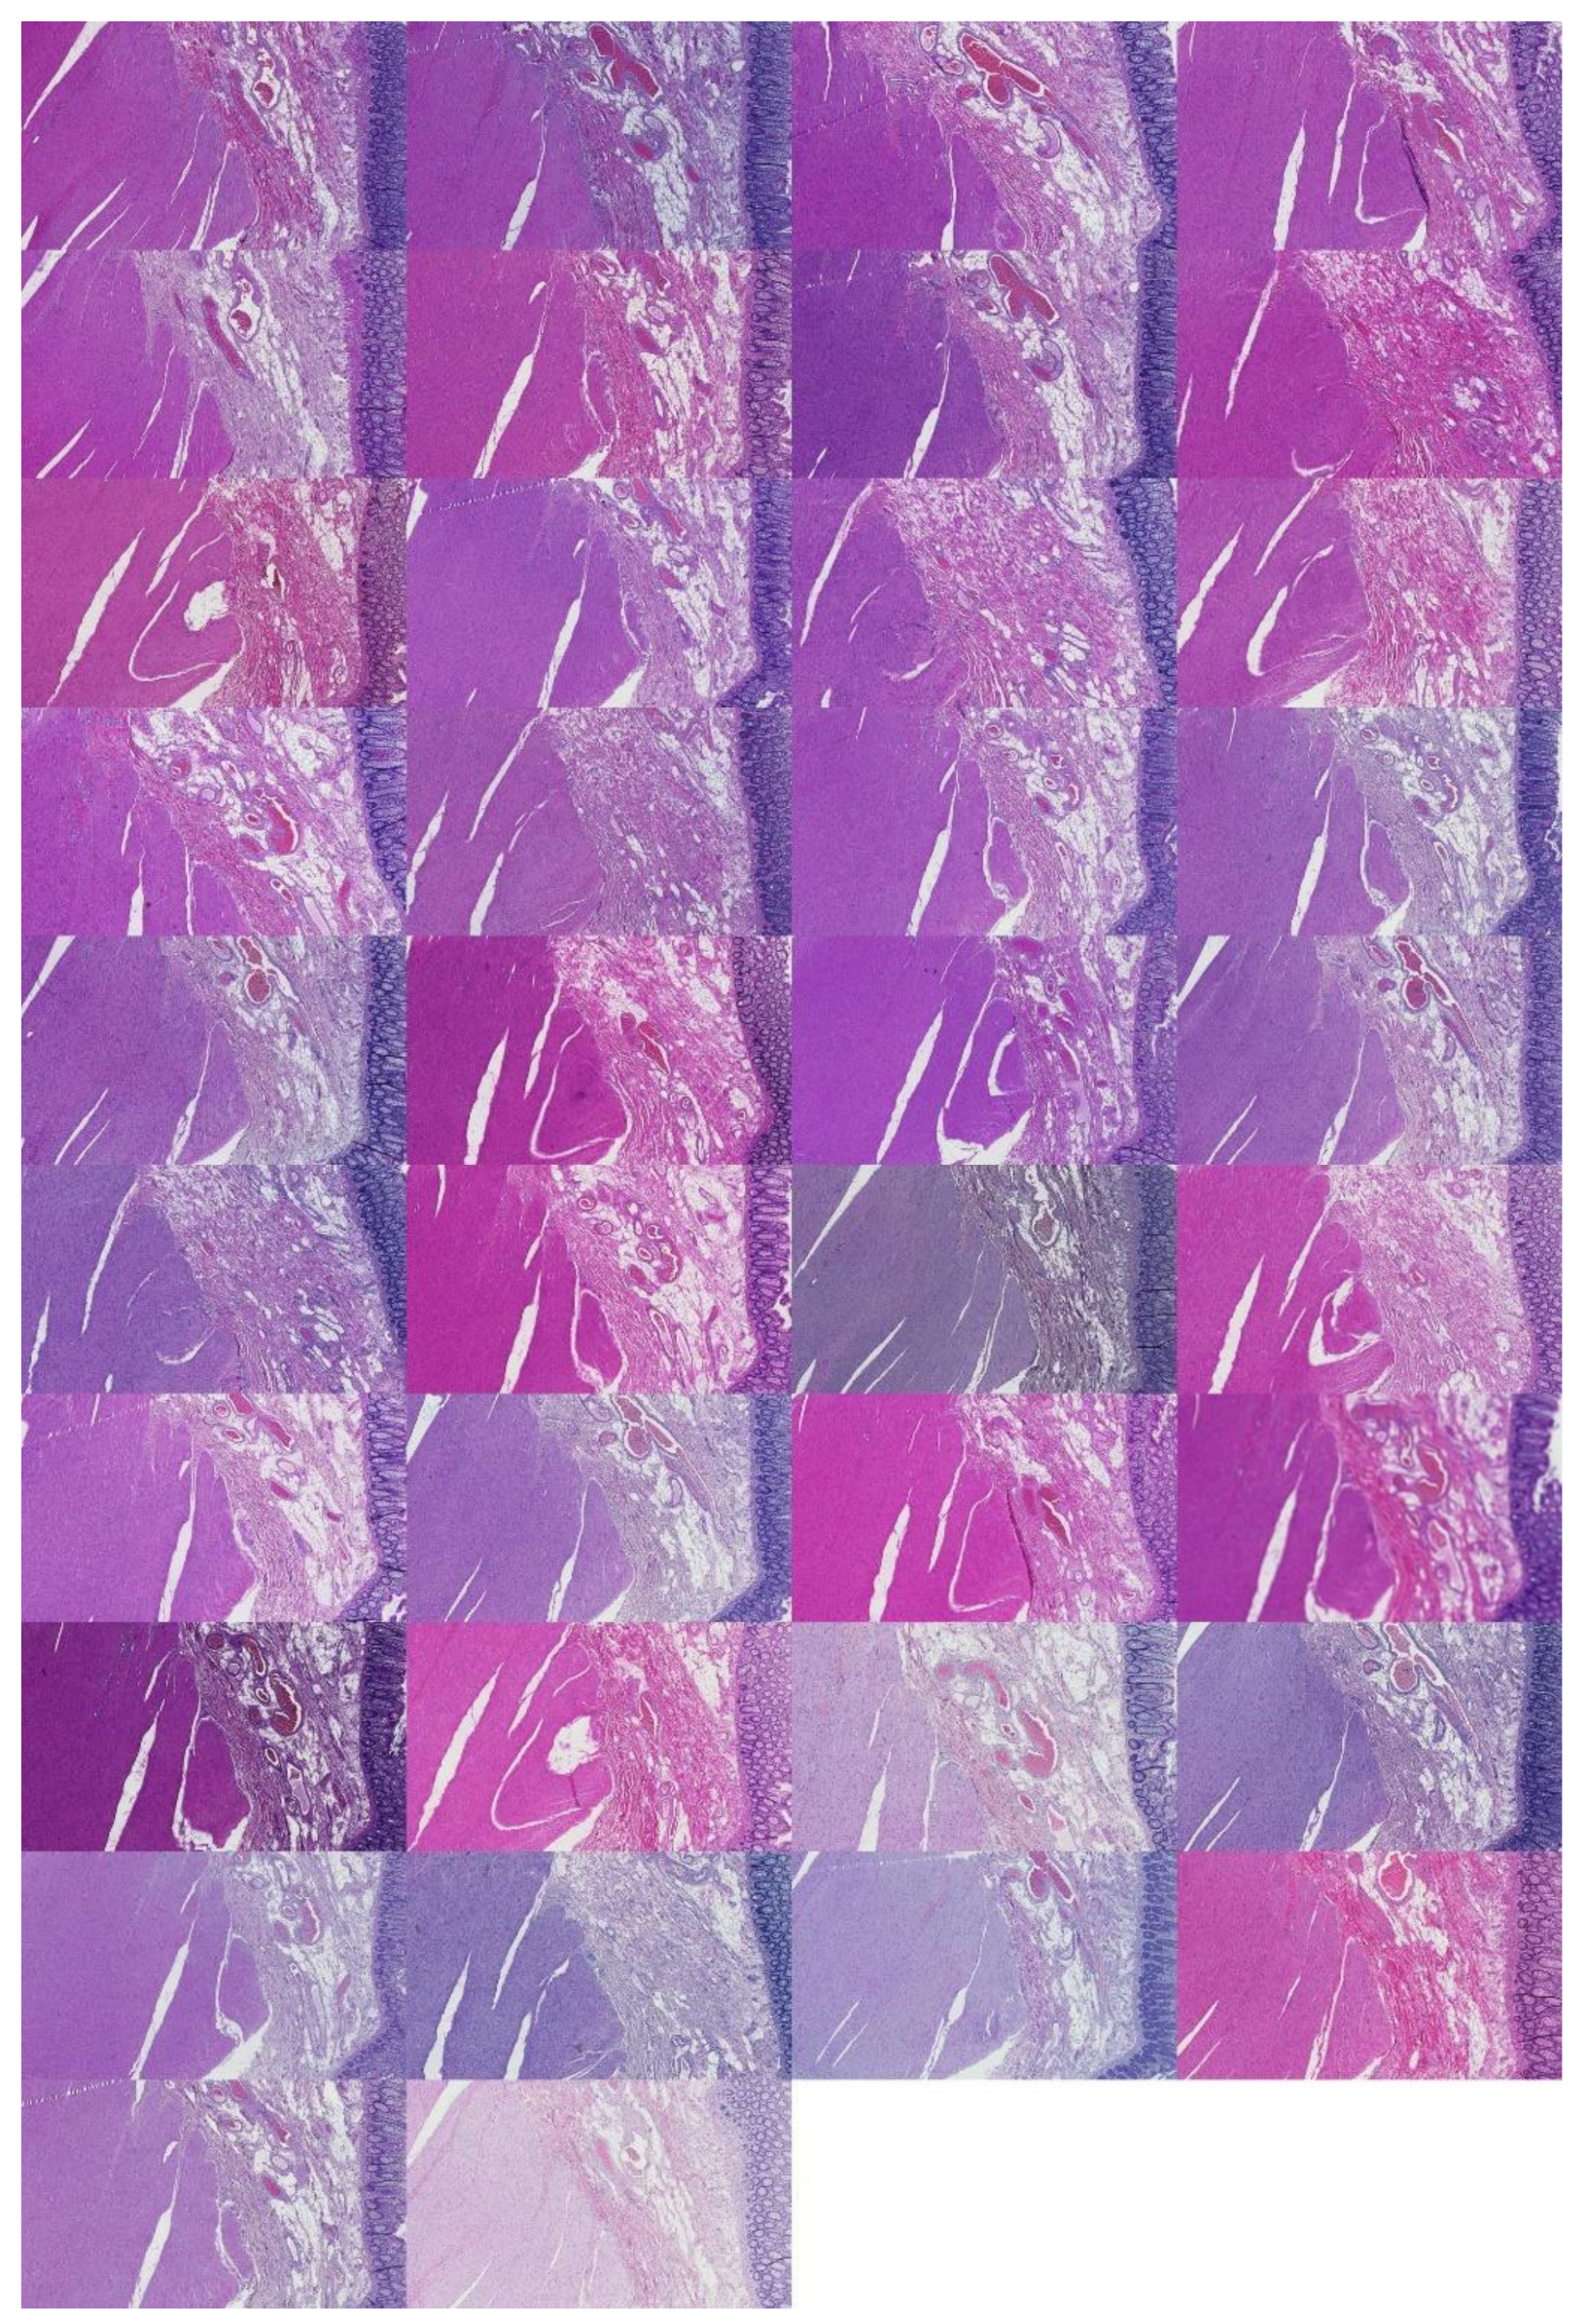

The preprocessing stage began with 66 WSI scans; we digitally cropped one region of interest (ROI) of size 1440 × 904 pixels for each tissue type in each slide. This resulted in three sets of images of 66 ROIs each, one set for the kidney, one for the skin, and one for the colon tissue. Cropping was used to minimize the presence of the non-tissue-related background, such as dust, hair, fibers, and other artifacts from previous preprocessing steps. The selected region coordinates were approximately the same within each tissue type. Each ROI was localized to cover an approximately sufficient area in each tissue type. Figure 3 shows samples of such ROIs for each tissue type amongst nine randomly chosen laboratories (three laboratories per tissue type).

Figure 3.

For illustration purposes, three ROIs from three laboratories per tissue type (column-wise). The first column is skin, the second column is kidney, and the last column is colon.